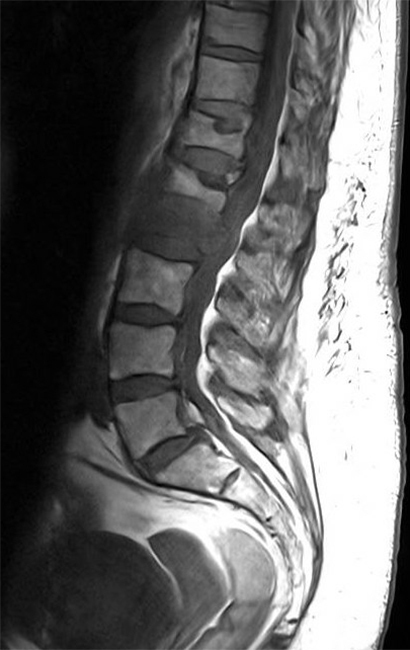

L’IRM rachidienne réalisée montre l’image suivante et le radiologue confirme le caractère suspect de malignité de la fracture. L’examen clinique de la patiente est inchangé. La masse pulmonaire a été biopsiée et vous êtes en attente des résultats. Figure 3 (Salomé Abdellaoui, La Revue du Praticien)

Figure 4 (Salomé Abdellaoui, La Revue du Praticien) L’imagerie montre une fracture de L2 en hyposignal T1 avec un recul du mur postérieur, ainsi que des fractures consolidées des plateaux vertébraux supérieurs de T12 et L1. Les fractures suspectes avec recul du mur postérieur sont réputées instables et nécessitent un avis orthopédique avant d’autoriser la mobilisation. En attendant l’avis ou en cas de fracture instable, on recommande un repos au lit strict et des mobilisations avec port d’un corset rigide. Un avis oncologique est recommandé devant cette forte suspicion de néoplasie, afin d’orienter la prise en charge et de débuter le suivi par une équipe dédiée. La biopsie est indispensable pour confirmer le diagnostic de cancer, mais le traitement ne pourra (dans l’immense majorité des cas) être débuté qu’après réception des résultats histologiques.